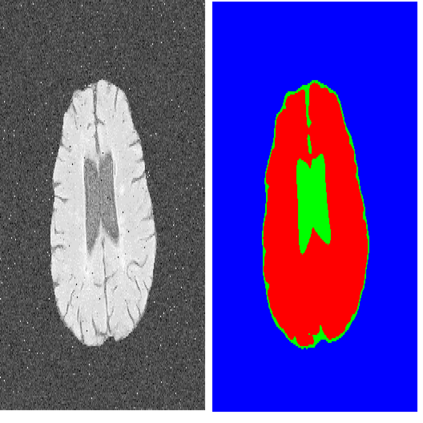

Semantic Segmentation(语义分割)

语义分割还是比较常见的,就是把图像中每个像素赋予一个类别标签(比如汽车、建筑、地面、天空等),比如下图就把图像分为了草地(浅绿)、人(红色)、树木(深绿)、天空(蓝色)等标签,用不同的颜色来表示。

不过这种分割方式存在一些问题,比如如果一个像素被标记为红色,那就代表这个像素所在的位置是一个人,但是如果有两个都是红色的像素,这种方式无法判断它们是属于同一个人还是不同的人。也就是说语义分割只能判断类别,无法区分个体。